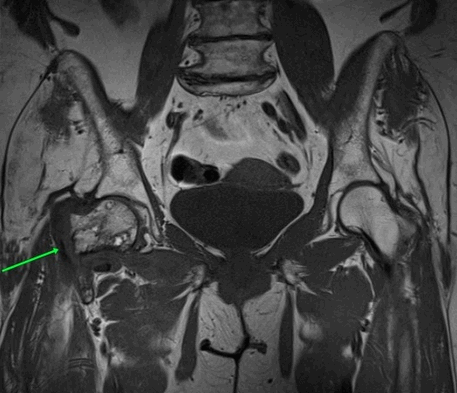

МР-признаки базисцервикального перелома шейки правой бедренной кости с наличием зон инфаркта головки и шейки правой бедренной кости, синовита правого тазобедренного сустава, отека окружающих мягких тканей справа.